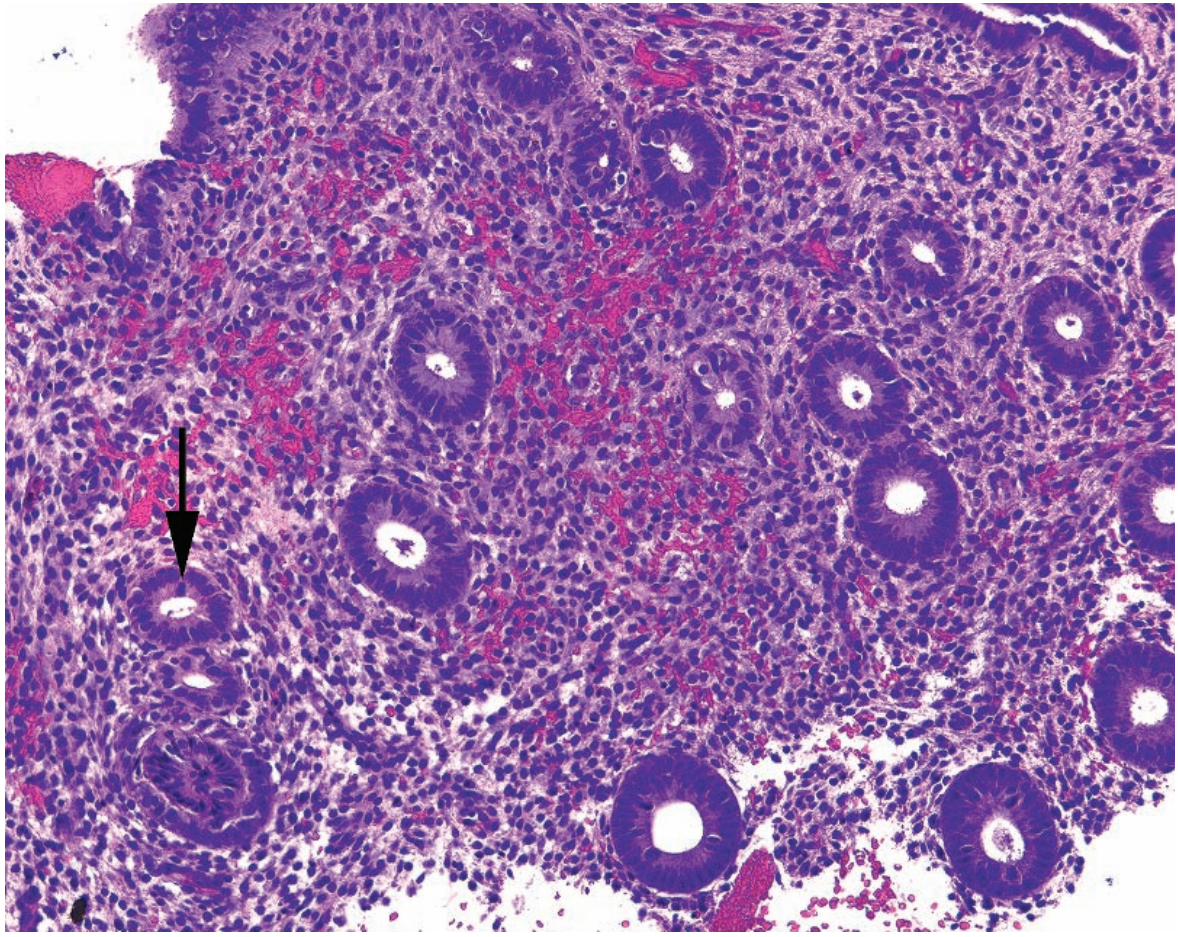

51

Leiomyoma Arrow/Arrowhead: Parallel and perpendicular bundles Inset: "Corkscrew" nuclei

What are some of the various morphologies that fibroids can take on? Summarize their typical morphology.

They can be myxoid or necrotic while still being benign. Spindle cell lesion with intersecting fascicles, corkscrew nuclei, and a fibrotic to myxoid or even hemorrhagic stroma.

Describe three morphologic criteria of leiomyosarcomas.

Many mitoses (\>10/10hpf) Cytologic atypia Coagulative necrosis